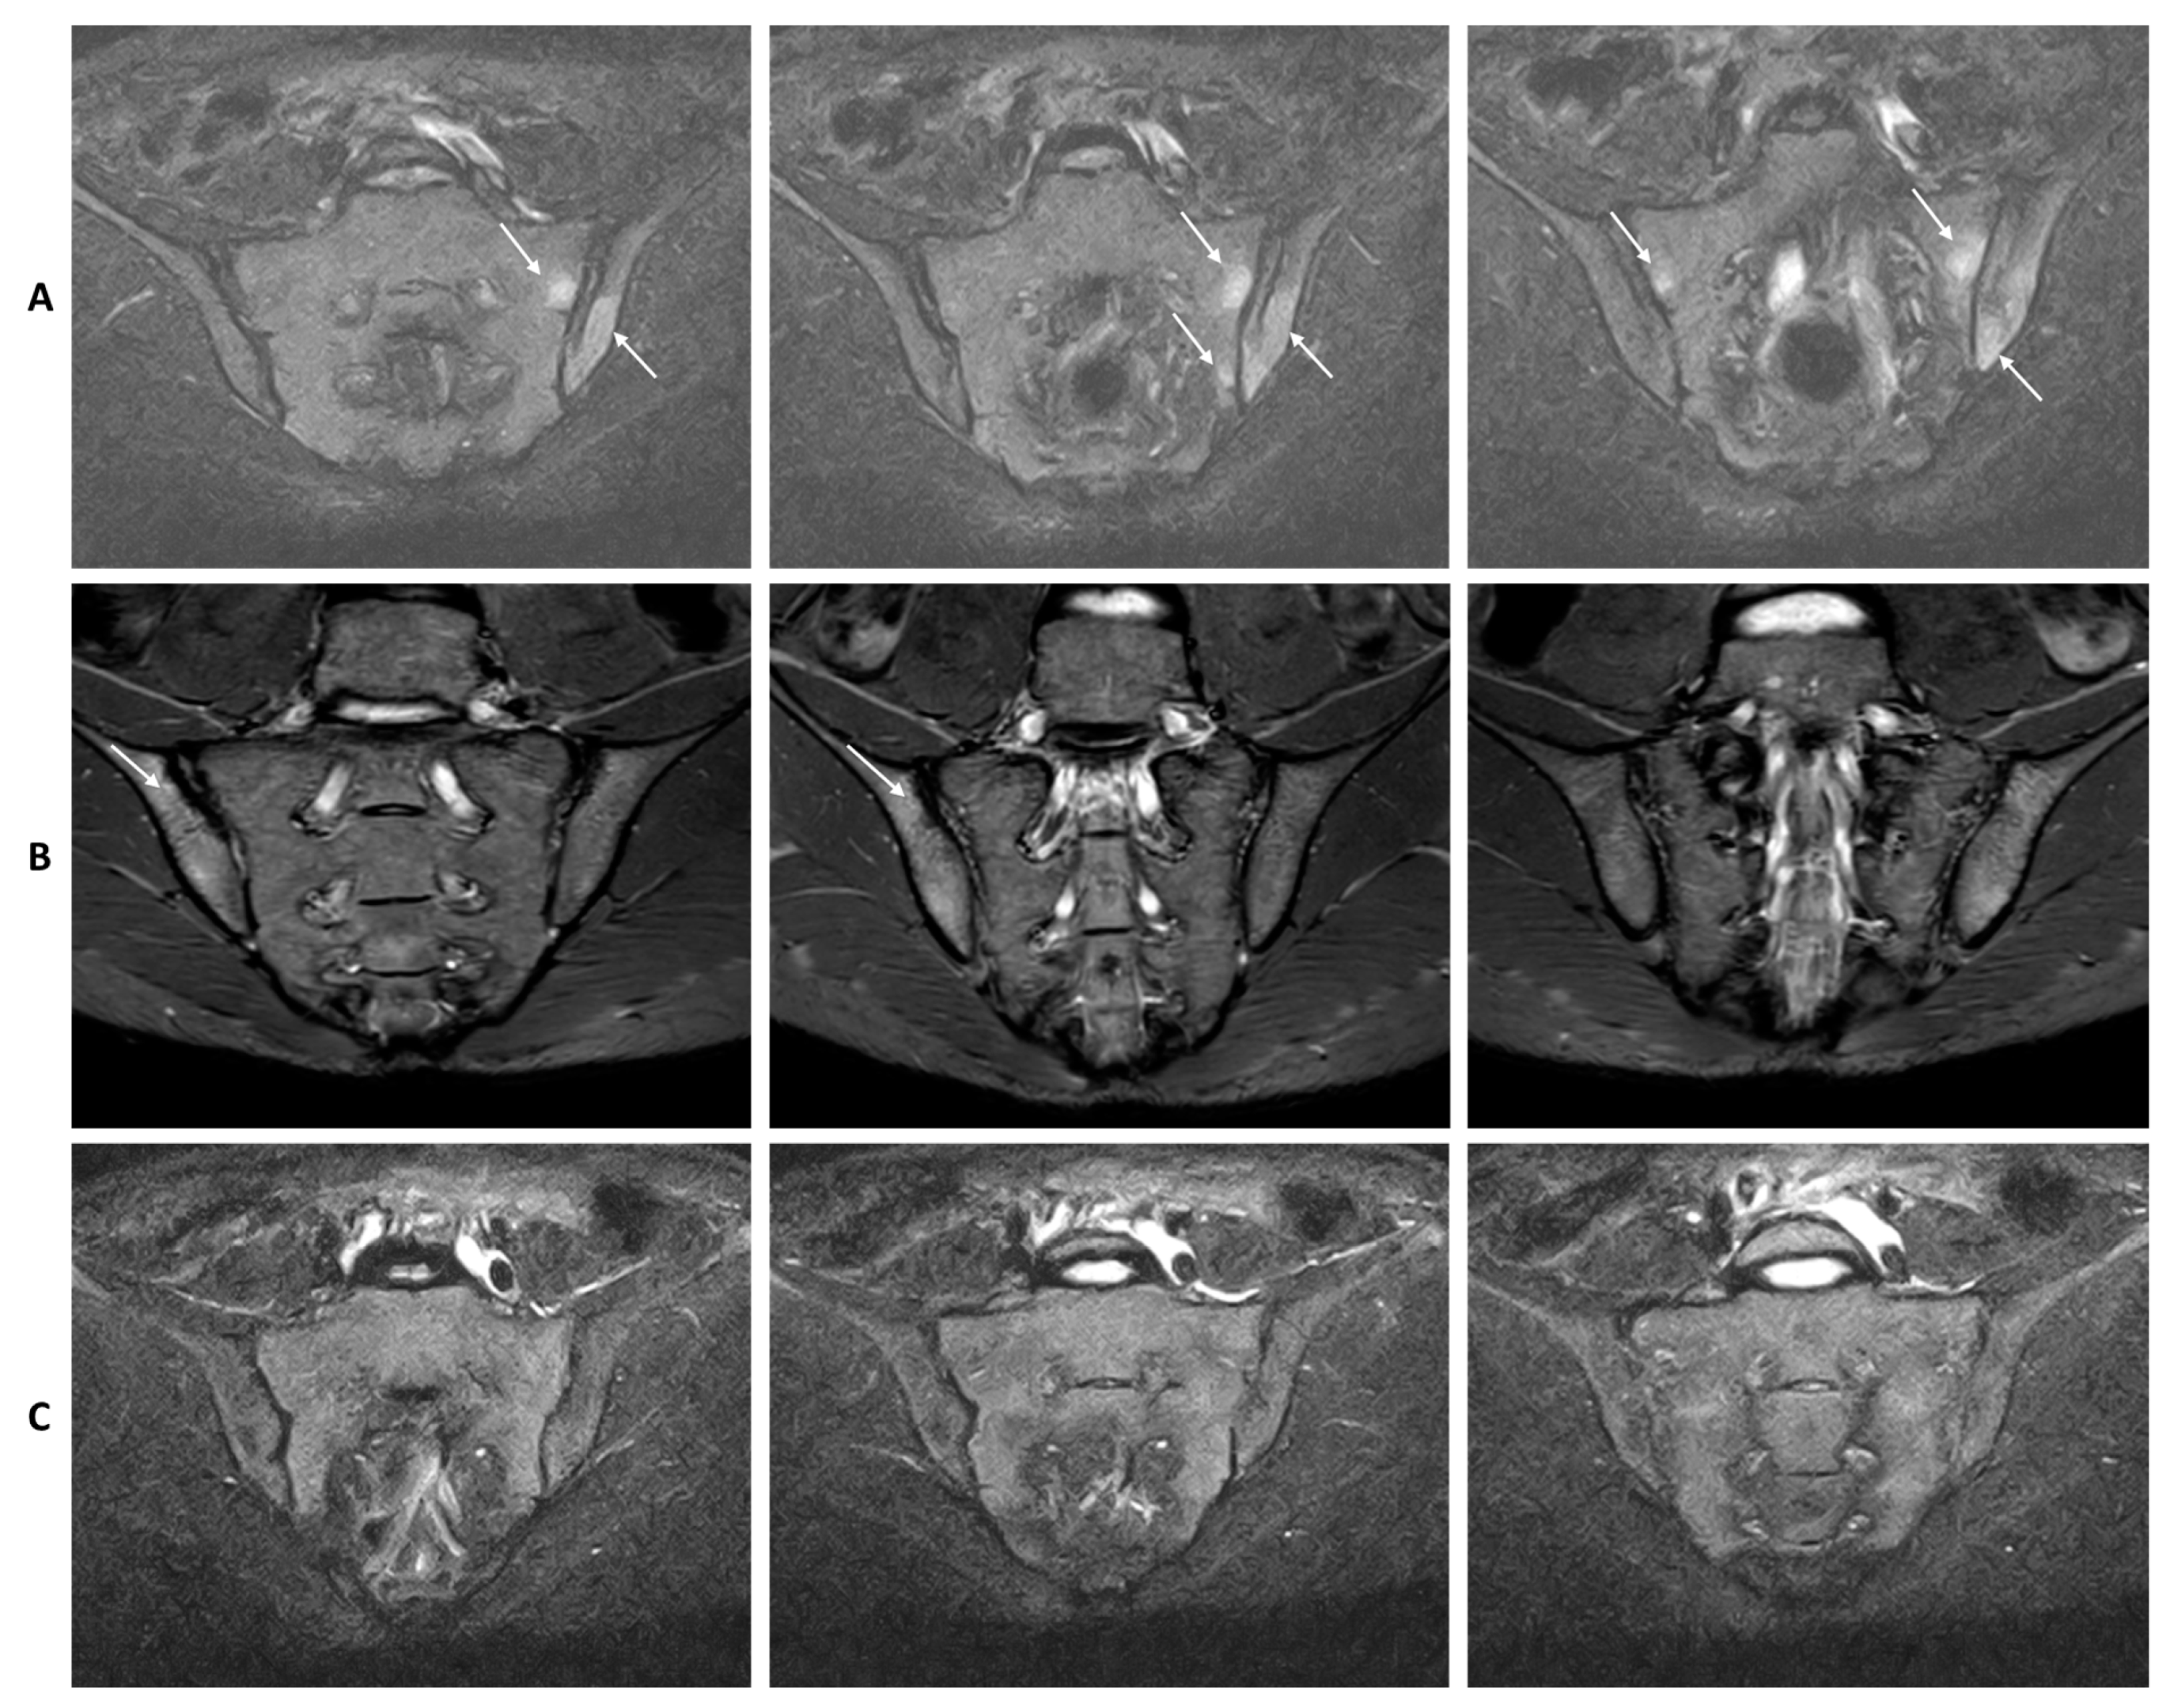

2.4. MRI Protocol and Interpretation of MRI Findings

4.4. MRI Findings